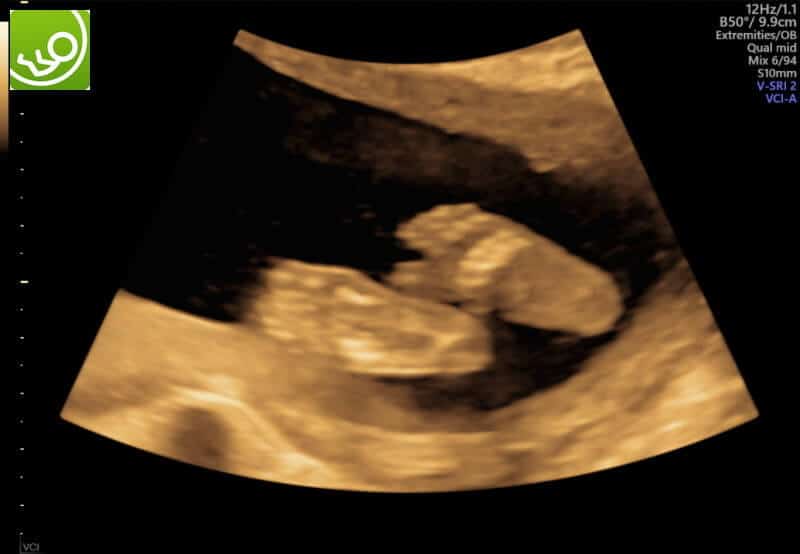

Und dann sagt sie – wieder in ihrer direkten und emphatischen Art: Der Magen gefällt mir nicht, der ist zu voll. Und im Darm ist auch eine kleine Blase zu erkennen. Ich muss ihnen leider mitteilen, dass ich noch den Verdacht des Double Bubble Syndroms erkenne. Die passende Diagnose wäre – wenn sich der Verdacht bestätigt – eine Duodenalatresie. Ein Verschluss des Zwölffingerdarms, so dass nichts, was sich im Magen befindet, auf den Weg durch den Darm machen kann. Daher entstehen zwei Blasen mit Flüssigkeit (einmal Magen, einmal Darm), was diesem Syndrom den Namen gibt.

Dadurch, dass sich der Magen nicht in Richtung Darm entleeren kann, gibt es kurz nach der Geburt eine Sonde, damit der Magen sich leeren kann und das Kind wird Intravenös versorgt. Stillen wird nichts bringen, da die Milch den Verdauungstrakt nie erreicht. Eine OP steht dann in den ersten Lebenstagen an, die sich sehr pragmatisch anhört: der Darm vor und hinter dem Verschluss oder der Engstelle werden einfach aneinandergenäht. Wenn alles gut geht, sind Kinder die nur dieses Krankheitsbild haben, nach 10 Tagen zu Hause.